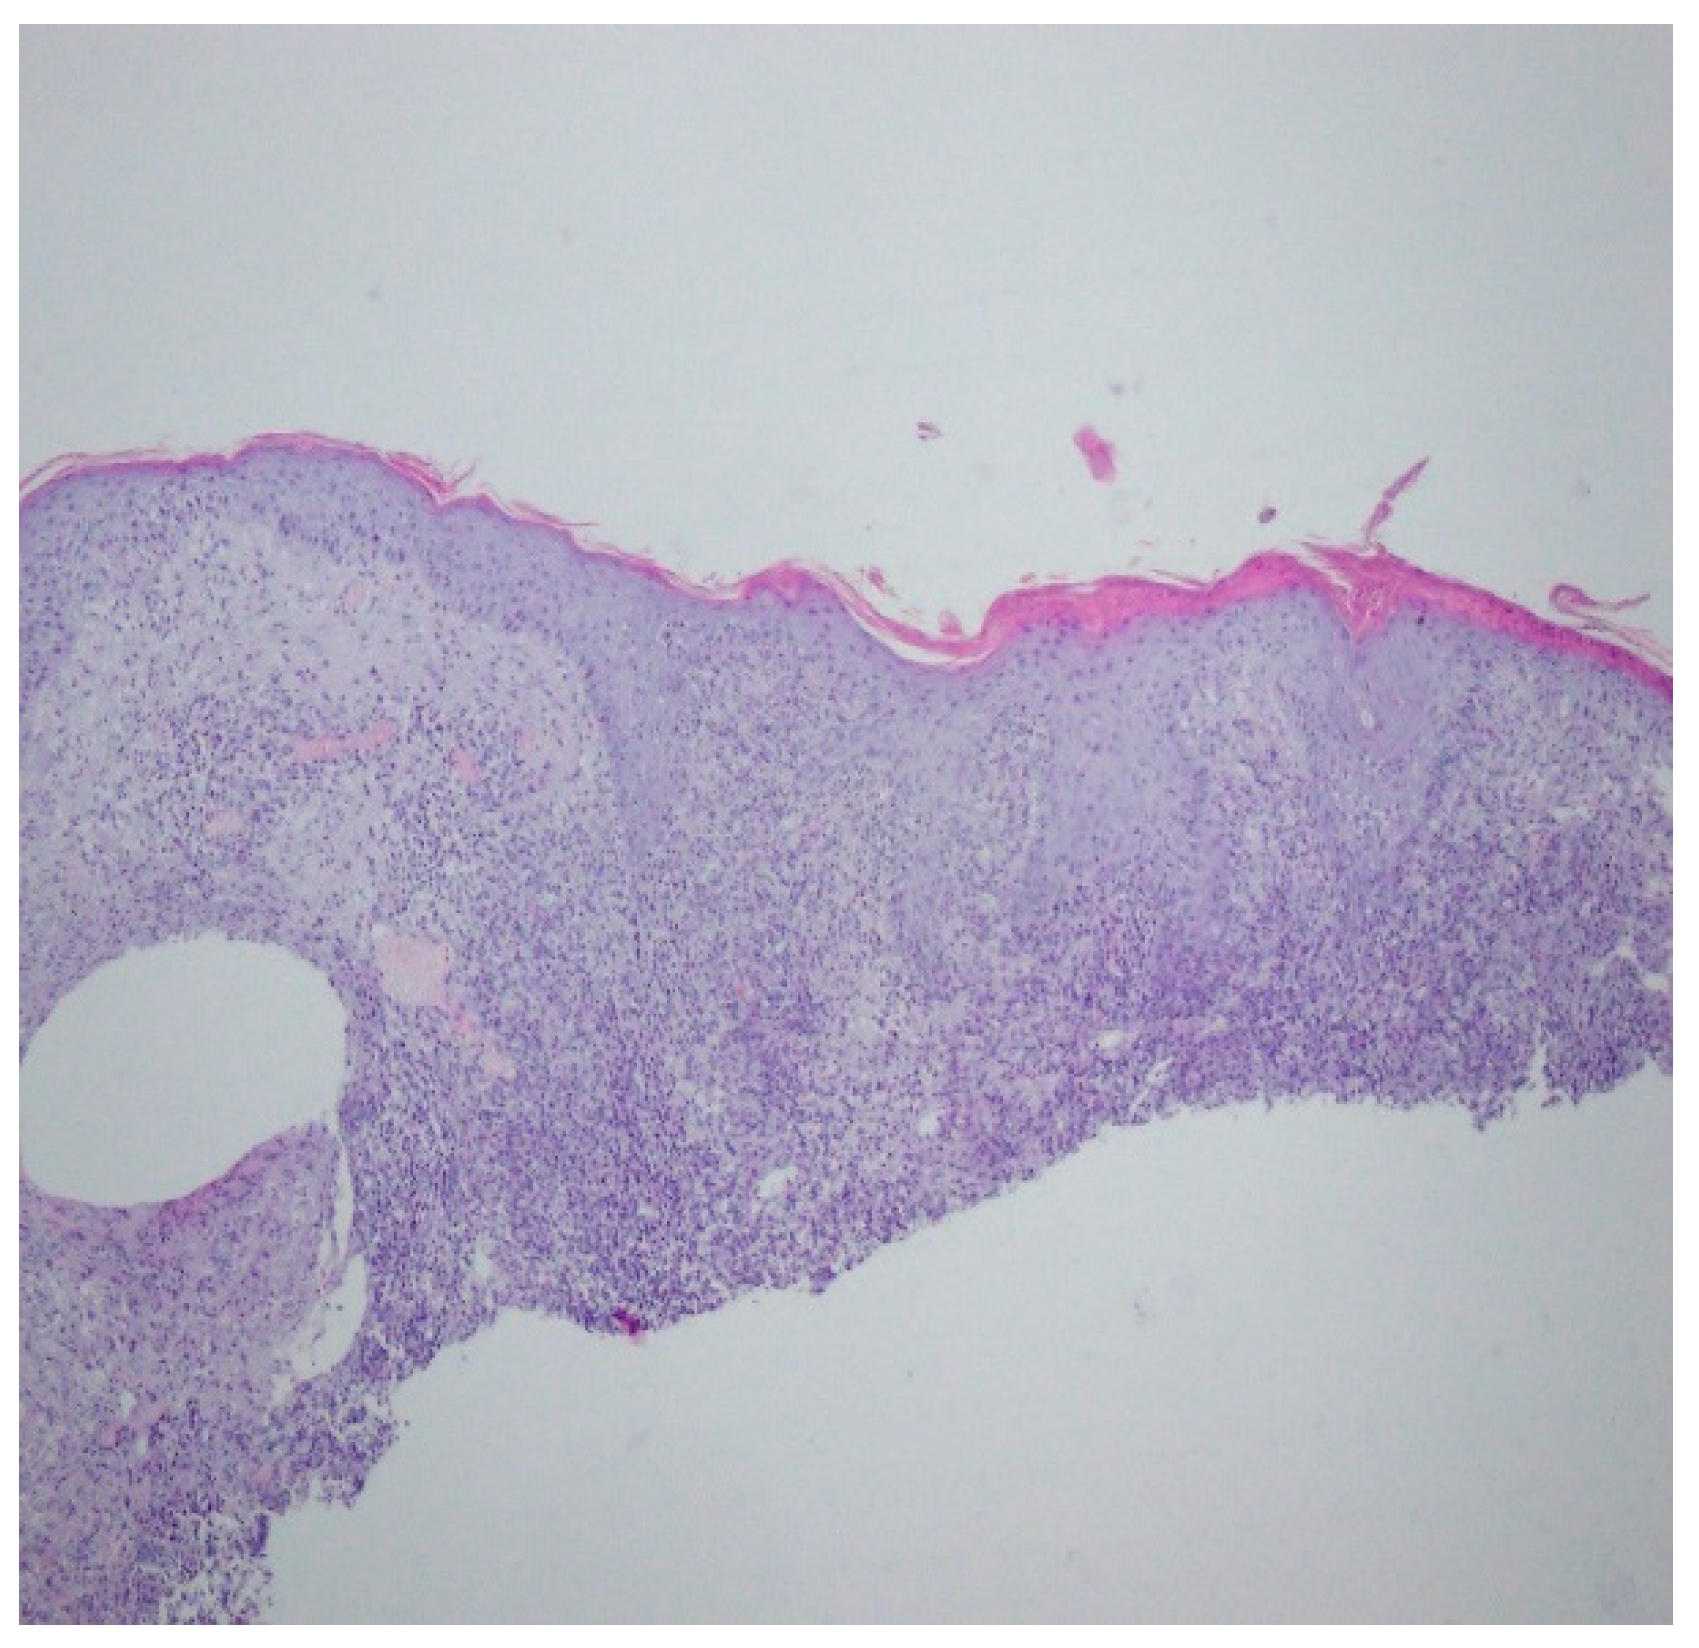

A histopathological examination of the skin lesion performed during hospitalisation revealed a thickened non-regular epidermis with streaky swelling, thinned by lymphocytic and histiocytic inflammatory infiltration with single plasmacytes. Slightly thicker infiltration presented in the area of enlarged vessels of the superficial plexus. There was a lack of characteristics typical for active pyoderma gangrenosum. This clinical picture can be consistent with secondary/tertiary syphilis (Figure 8 and Figure 9).

Figure 8.

Thickened non-regular epidermis with streaky swelling, thinned by lymphocytic and histiocytic inflammatory infiltration with single plasmacytes. Slightly thicker infiltration in the area of enlarged vessels of the superficial plexus. Lack of characteristics typical for active pyoderma gangrenosum. The clinical picture can be consistent with secondary/tertiary syphilis.

Figure 9.